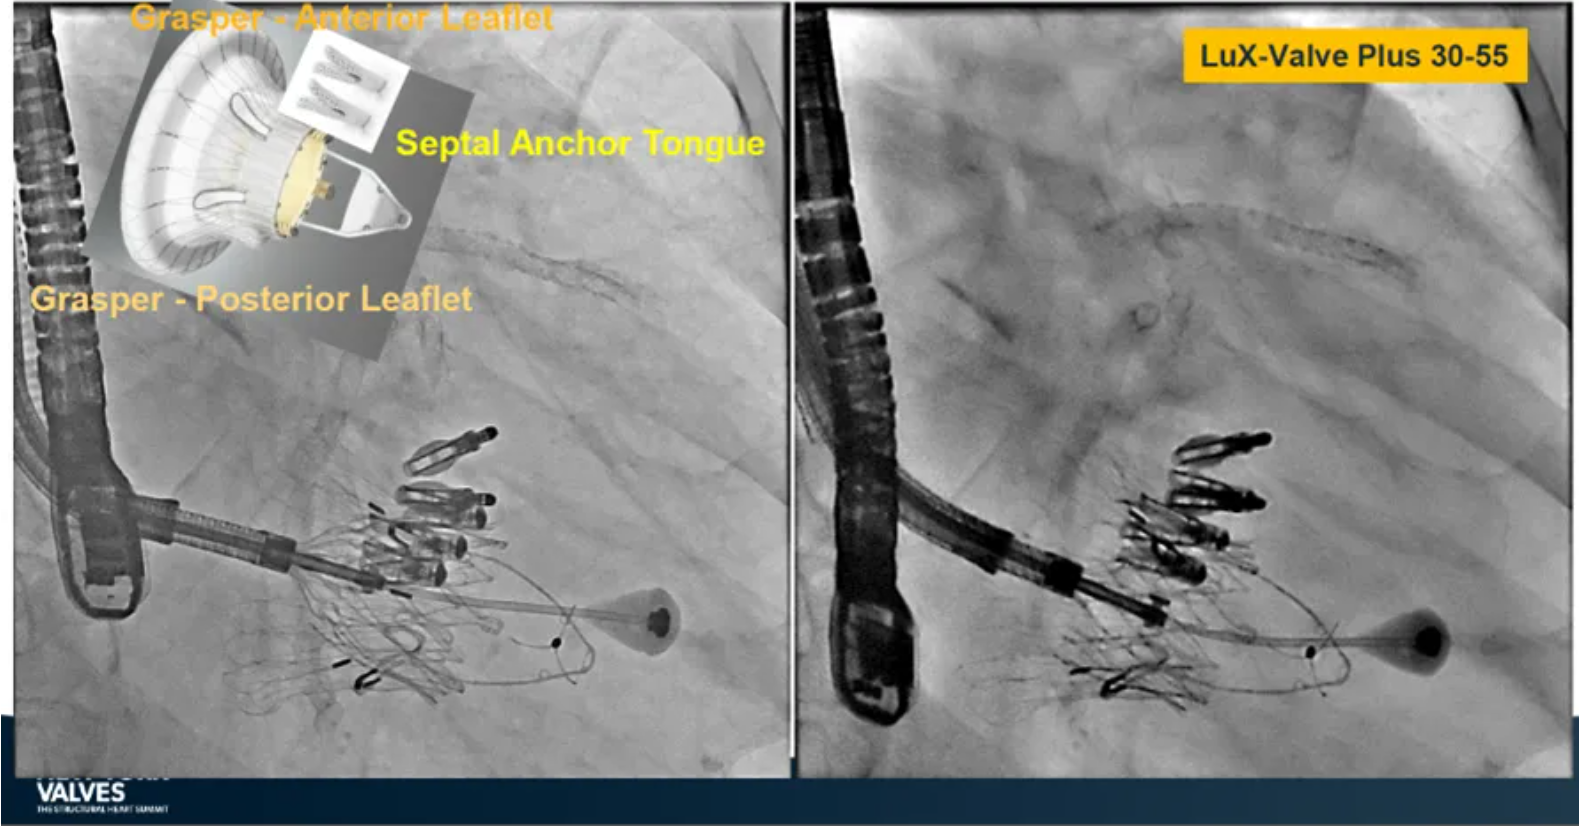

來自中國香港瑪麗醫(yī)院(Queen Mary Hospital, Hong Kong, China)的Simon Lam教授在2024紐約瓣膜會上分享了一例復(fù)雜案例,一名高齡男性患者在2年前行二尖瓣和三尖瓣TEER術(shù)式后繼發(fā)三尖瓣反流,遂再次行二尖瓣TEER術(shù)式和用LuX-Valve Plus行三尖瓣TTVR術(shù)式。

本次術(shù)式中,LuX-Valve Plus的植入緊隨二尖瓣修復(fù)術(shù)式之后,且并未取出前期植入的三尖瓣修復(fù)夾,這意味著LuX-Valve Plus在患者有過二尖瓣和三尖瓣修復(fù)夾植入情況下的兼容性,并且?guī)砹擞行У闹委熃Y(jié)果。此外,這不僅體現(xiàn)了LuX-Valve Plus可以與二尖瓣術(shù)式并行,更可以兼容三尖瓣原位的其他修復(fù)夾產(chǎn)品。